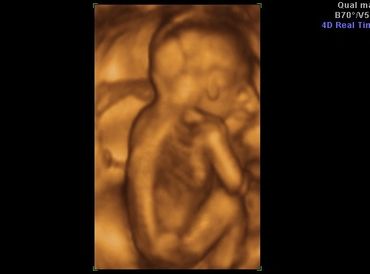

All our providers do their own ultrasounds in the office during your visit. We are known for our ultrasounds and do at least four with each pregnancy. And we can record your ultrasound on a USB device for you to take home and share!